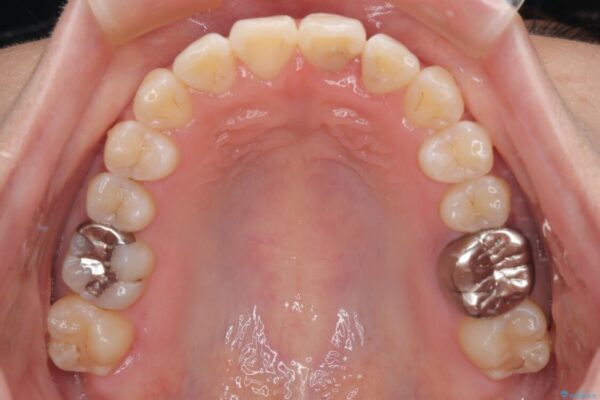

矯正治療期間はわずか10か月と、比較的短期間で終了しました。

前歯のデコボコがなくなり、見た目の印象が大きく変わっただけでなく、歯磨きがしやすくなり、むし歯や歯周病のリスクが大きく減少しました。

治療後

• 前歯のねじれ・ガタガタを10か月で改善!20代女性の矯正治療|クリアブラケットでむし歯になりにくい歯並びへ改善 治療後画像